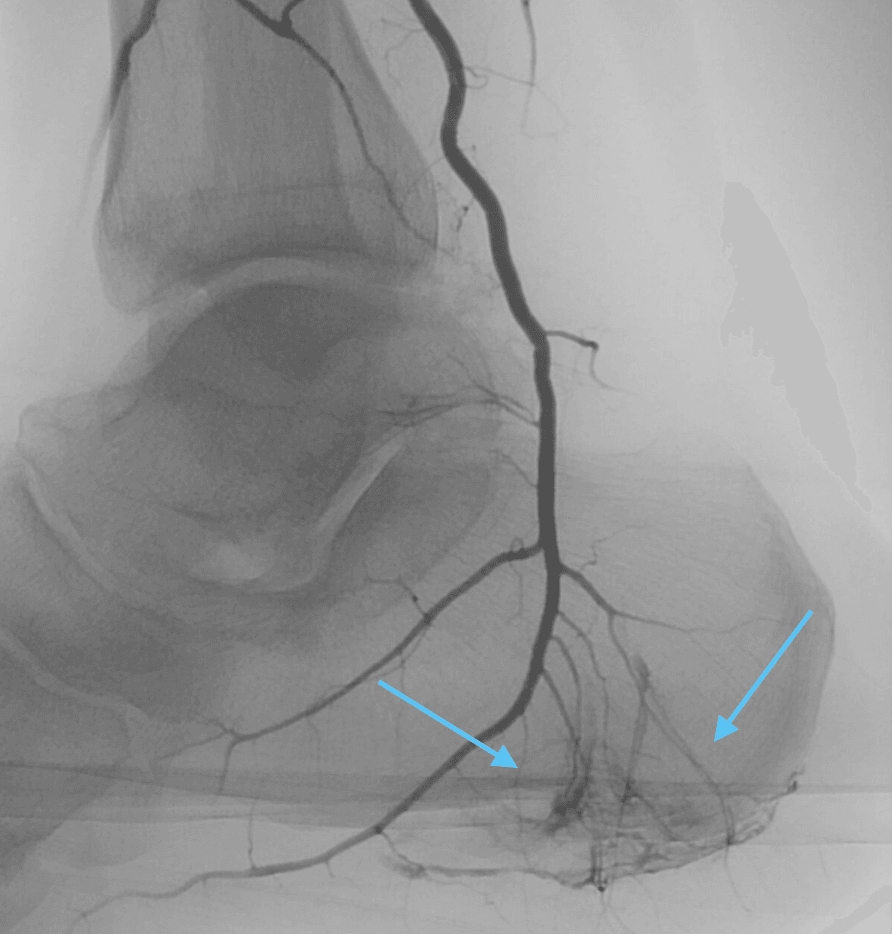

In cases of chronic plantar fasciitis, researchers have observed an increase in abnormal neovascularization (the growth of new blood vessels) around the inflamed plantar fascia. These new blood vessels are believed to contribute to the chronic inflammation and persistent pain associated with the condition. Embolization works by blocking these abnormal blood vessels, thereby reducing blood flow to the inflamed tissue, which in turn decreases inflammation and promotes healing.

After a small numbing injection, a tiny “IV like” catheter is inserted into the blood vessel at the ankle, using real-time ultrasound and sometimes x-ray imaging. Once the catheter is in position, tiny embolic antibiotic agents are introduced into the blood vessels to block the abnormal vessels. The embolic agents cut off the blood supply to the abnormal vessels but leave normal vessels intact, reducing inflammation and pain in the affected area.